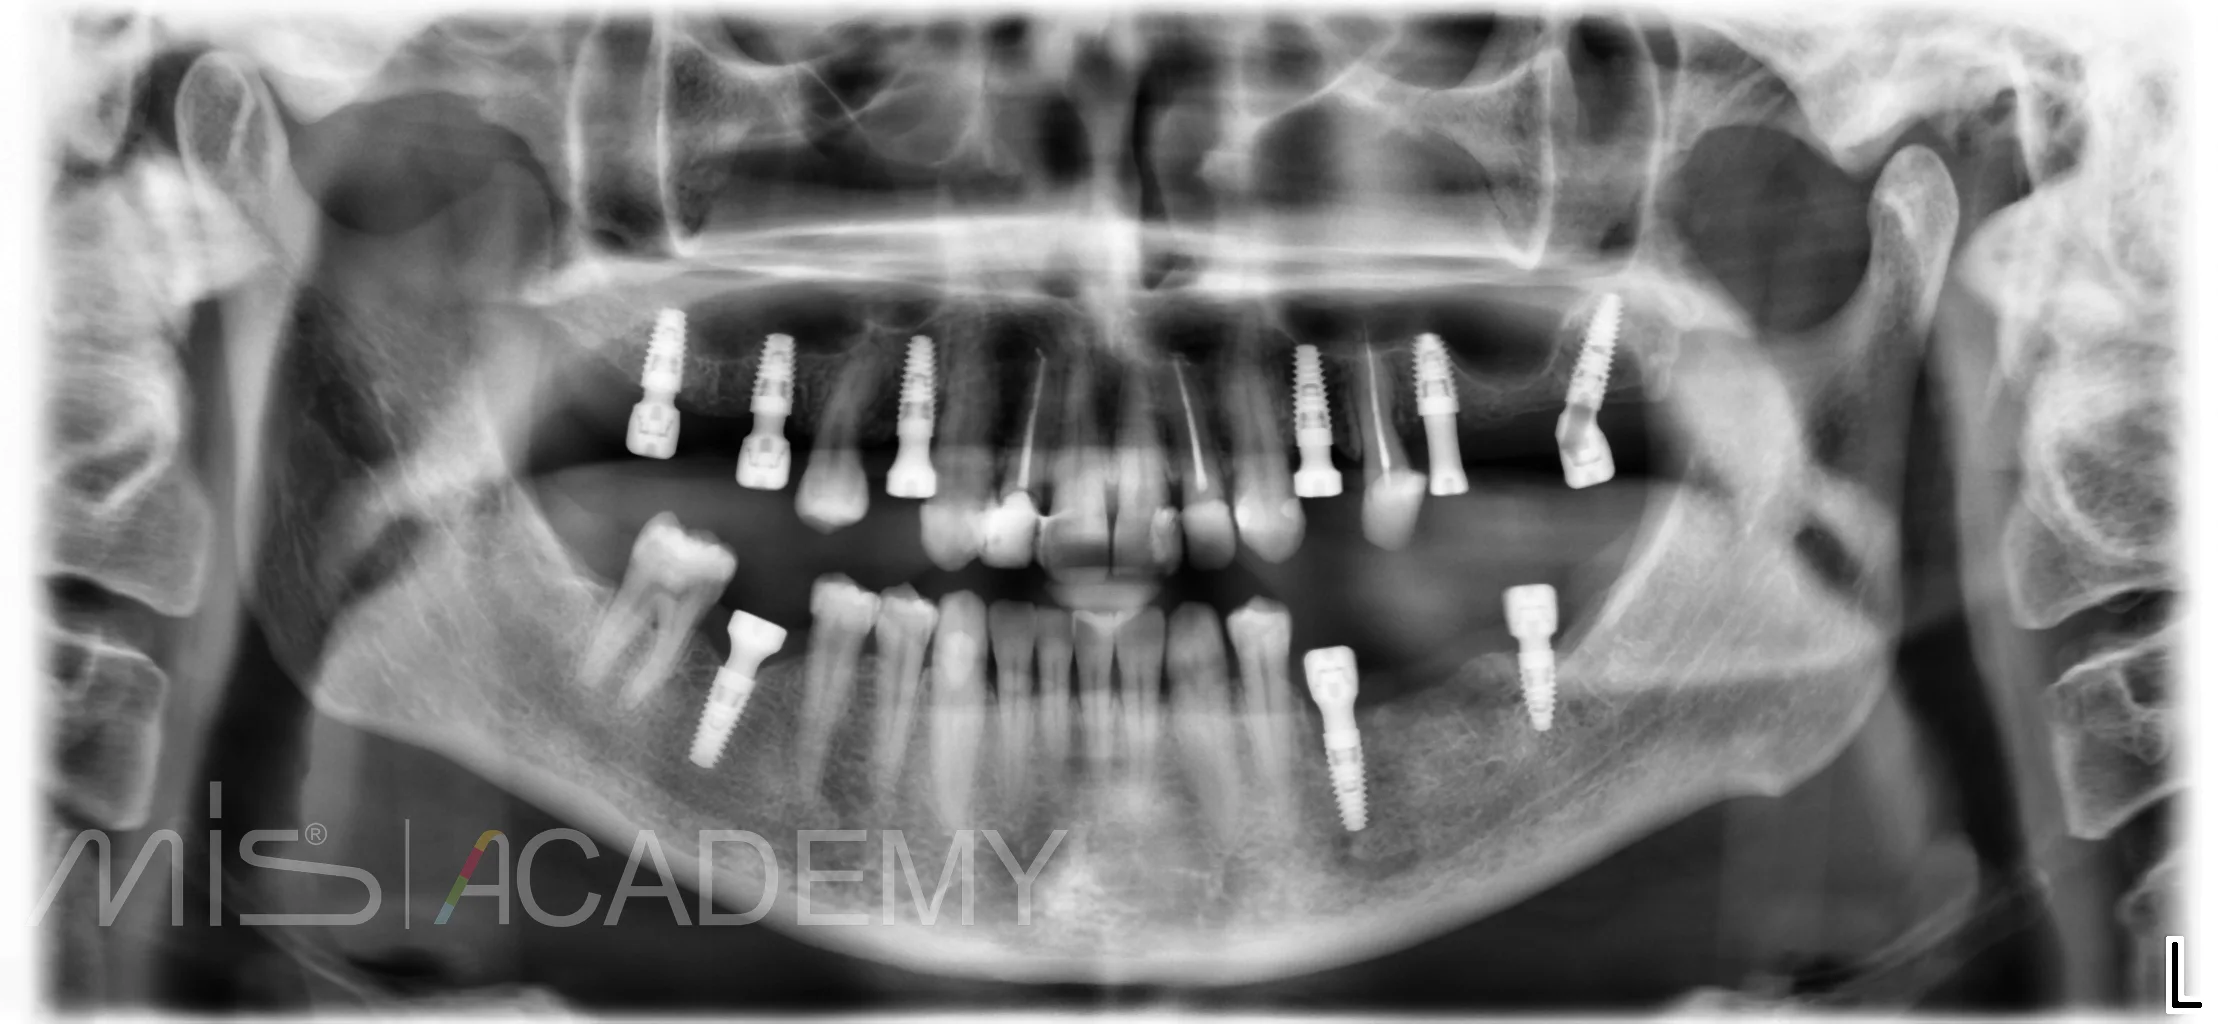

Установка имплантатов MIS C1 в области 46, 35, и 37 по навигации.

— Протезирование через 6 месяцев.